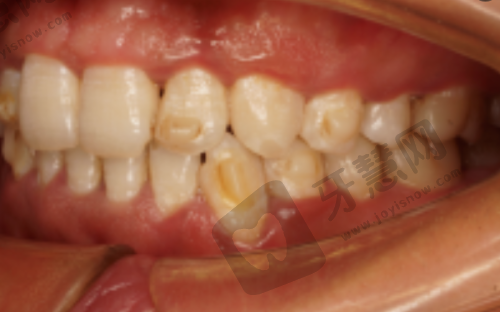

“我因为牙齿缺失,想做种植牙。来到德伦口腔(滨江分院)后,施卫东医生为我进行了详细的检查和评估。他推荐我做单颗牙微创种植,给我讲解了手术的过程和优势。手术过程非常顺利,施医生的技术真的特别棒,创口特别小,修复也特别快。现在我的种植牙使用起来和真牙一样,非常满意。德伦口腔的设备也特别精良,服务也特别周到,让我没有了后顾之忧。”